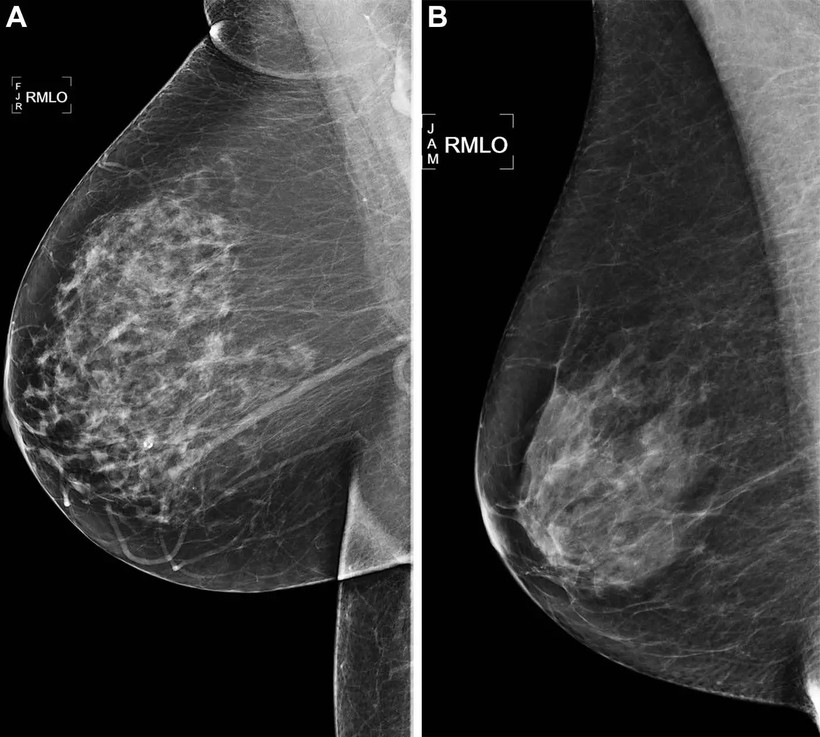

Ảnh quang tuyến vú sàng lọc xiên bên phải (RMLO)